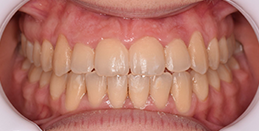

The facial changes are impressive considering treatment involved only conventional orthodontics and not orthopedic interventions, TADs, or surgery.

Dr. Coca concludes that improved biomechanical understanding of extreme crowding and torque management could have reduced treatment duration. From his experience, proper force management can facilitate bone remodeling, challenging the idea of bone limitations in orthodontics.

The teeth are in a very good position and the bone has reshaped.